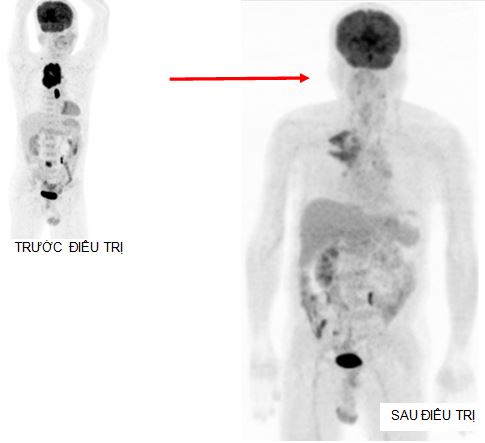

Đáp ứng điều trị: ngay sau chu kỳ hóa chất đầu tiên, bệnh nhân đã cảm thấy dễ thở hơn, không cần hỗ trợ thở oxy. Sau 3 chu kỳ hóa chất bệnh nhân được chụp PET/CT lần thứ hai để đánh giá đáp ứng điều trị.

Trước điều trị: - Khó thở, mất tiếng - CEA=19,78 ng/ml - KT u 5,6x6,5x9,0cm - Max SUV=13,18 - Tổn thương D2 tăng hấp thu FDG | Sau điều trị 3 đợt chu kỳ - Không khó thở, khàn tiếng - CEA=7,96 ng/ml - KT u 3,0x2,5x6,2cm - Max SUV=8,01 - Tổn thương D2 không tăng hấp thu FDG. |

Bệnh nhân tiếp tục được điều trị 3 đợt hóa chất Gemcitabine – Cisplatin + xạ trị vào khối u đỉnh phổi phải và hạch trung thất với tổng liều 66 Gy.

Sau khi kết thúc điều trị bệnh nhân không còn khó thở, sinh hoạt bình thường, chỉ còn khàn tiếng nhẹ, hết đau vai – ngực phải. Xét nghiệm CEA=3,72 ng/ml.